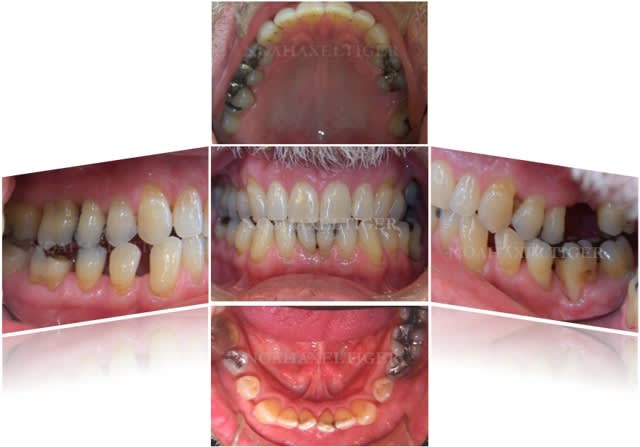

> voila comme promis les 2 cas cliniques.

>

> patiente 1 : paro aggressive, importantes lésions

> angulaires traitées par emdogain sauf mesial 33 où

> j'ai préféré faire une GTR avec comblement

> BioOss.

Superbes résultats !

Quelques questions :

1 La conservation de la 28 n'est elle pas un facteur défavorable ?

2 la 26 a t'elle été extraite en première intention ou après un échec de la régénération ?

3 avais tu dans ce cas une espèce bactérienne spécifique ?